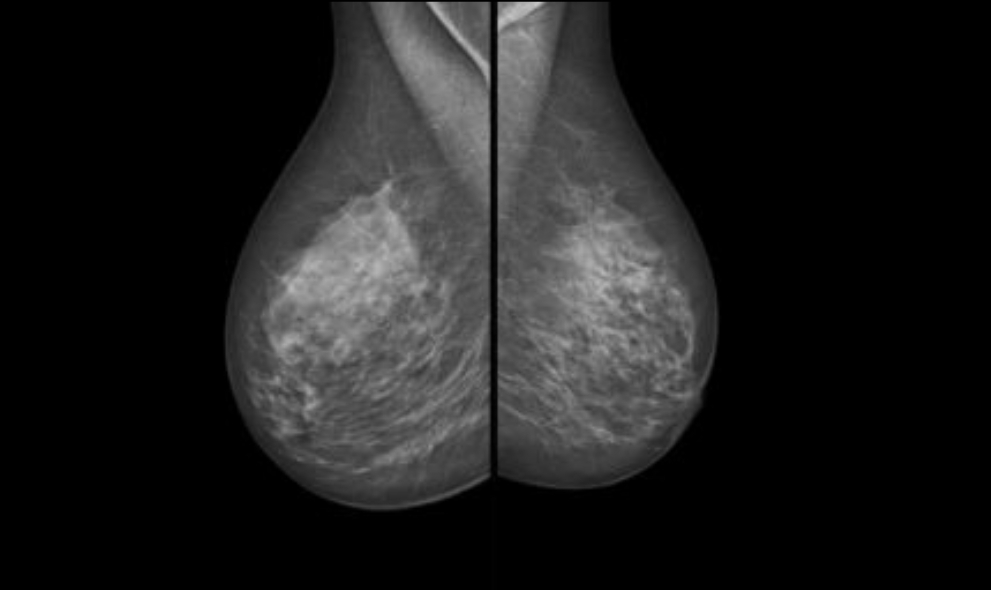

Mamografi, meme muayenesinde saptanamayacak kadar küçük anomalilerin tespit edilmesi amacıyla düşük dozda çekilen bir meme röntgen filmidir. Günümüzde en önemli meme kanseri teşhis yöntemidir. Erken teşhis amacı ile belirli bir yaştan sonra düzenli olarak çekilmesi önemlidir.

Mammografi, memenin rontgen filminin çekilerek, kanserin erken dönemde saptanmasına sağlayan bir yöntemdir. Bu yöntem ile, toplumda belirli bir yaşın üstündeki tüm kadınların meme filmi çekilerek, meme kanseri erken safhada yakalanmaya çalışılır. Bu şekilde toplumda meme kanseri taramasının yapılabildiği mamografiye, tarama mamografisi denir.

Tarama mammografisi, dünyada en yaygın kullanılan meme kanseri erken tanı yöntemidir. 40 yaş üzerindeki her kadının 70 yaşına kadar her yıl mamografi çektirmesini önermektedir. Yüksek riskli hasta durumlarında taramaya ultrasonografi ve magnetik rezonansta eklenebilmektedir.